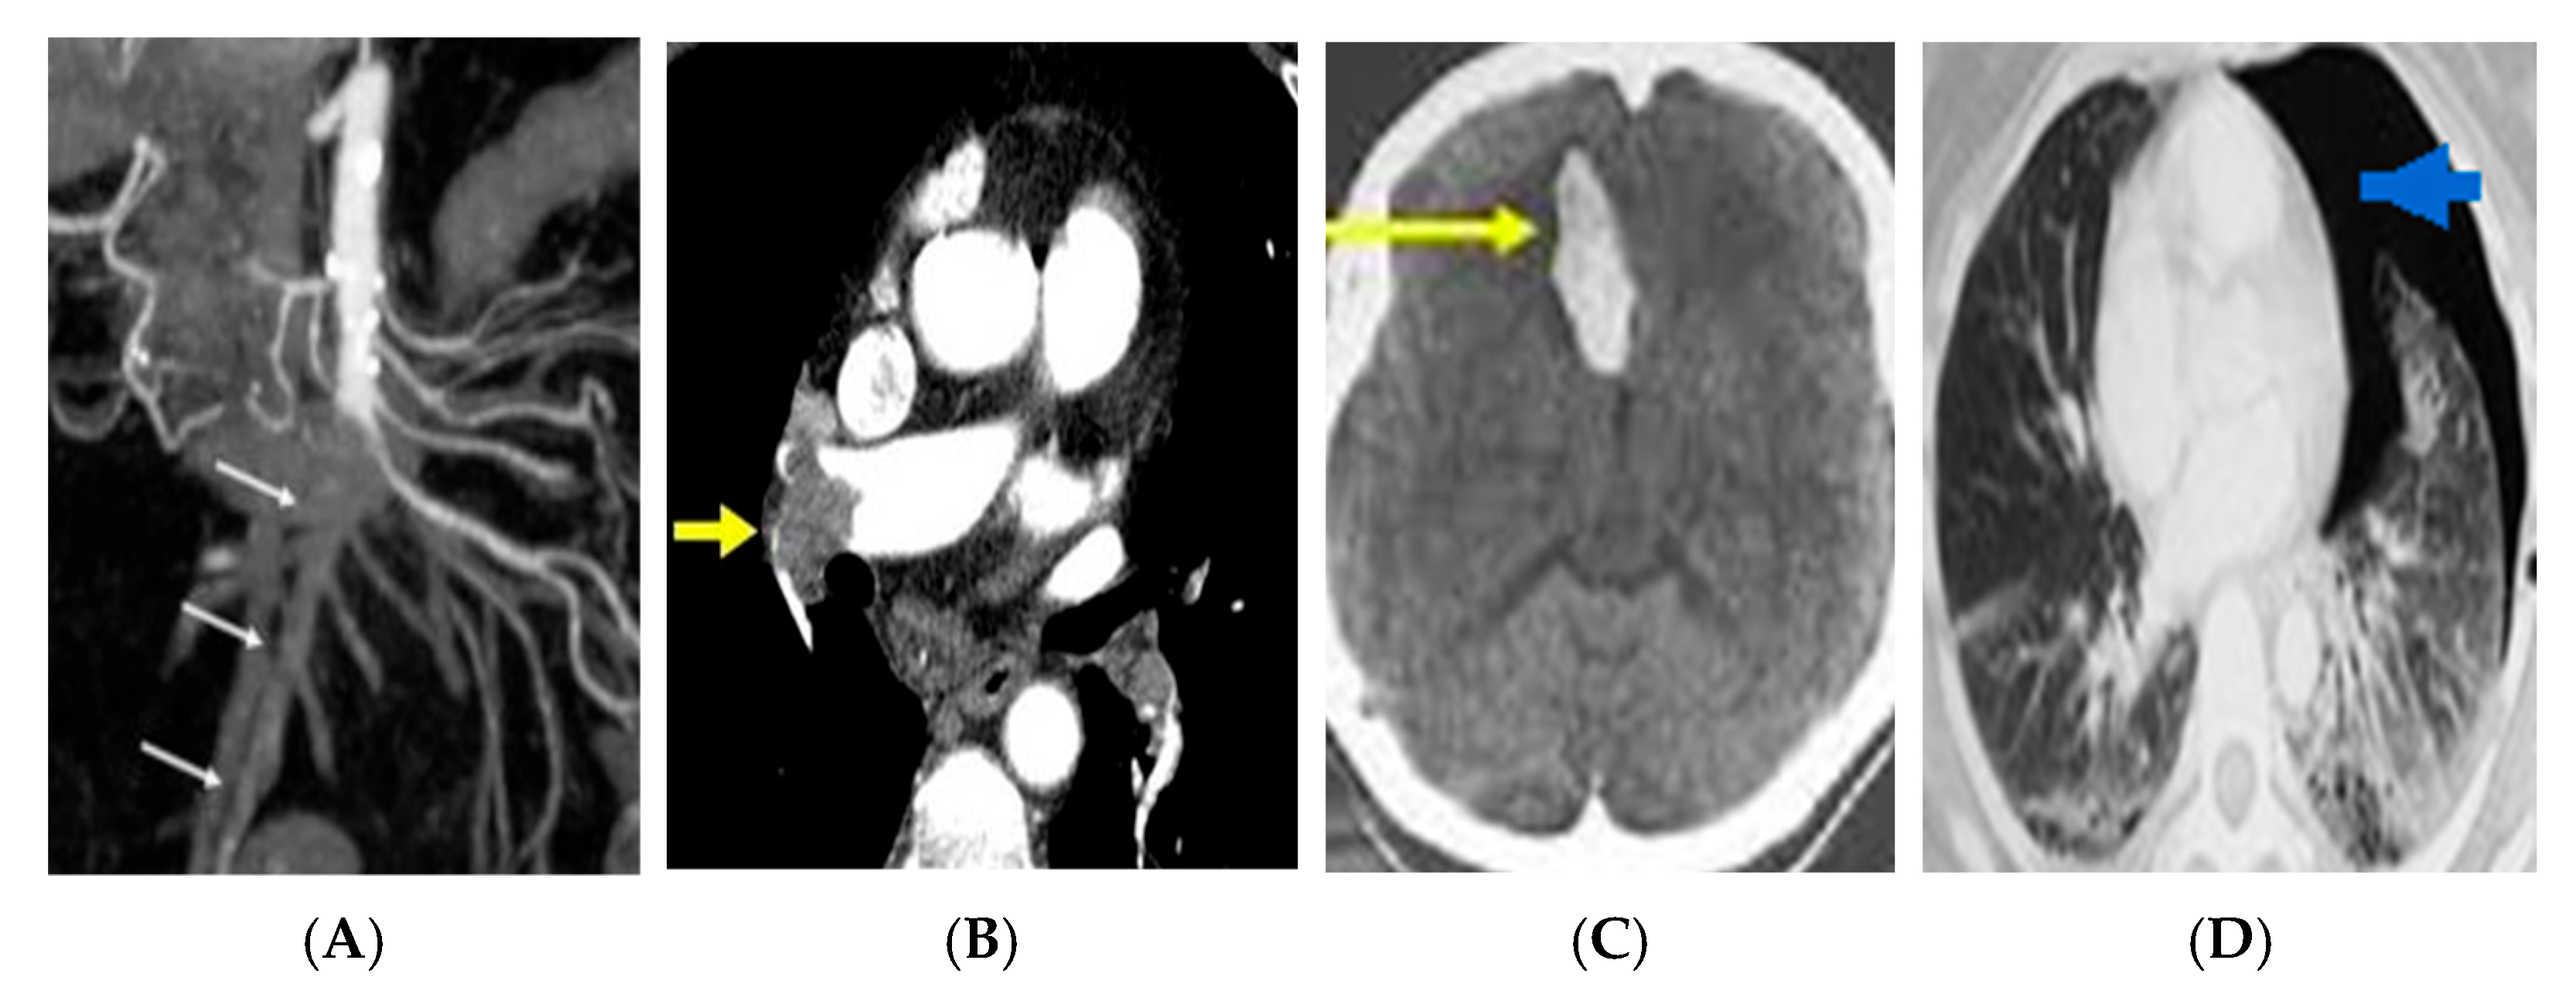

Representative anonymized imaging examples illustrating how key radiologic patterns are mapped into the framework are provided in Figure 2.

These anonymized examples illustrate how key imaging findings populate the “Imaging Findings” domain and connect to explicit decision/escalation nodes within the framework.

Figure 2. Representative anonymized imaging examples illustrating framework mapping across emergency scenarios. (A) Contrast-enhanced abdominal CT demonstrating imaging features consistent with acute mesenteric ischemia (mesenteric vessel occlusion; arrows). (B) CT pulmonary angiography demonstrating a pulmonary arterial filling defect consistent with acute pulmonary embolism (arrow). (C) Non-contrast head CT demonstrating acute intracranial hemorrhage (arrow). (D) Chest CT demonstrating pneumothorax (arrow).

Importantly, these observations arise from a controlled simulation setting and should not be interpreted as evidence of clinical effectiveness; empirical evaluation in real learners and clinical workflows is required. Representative anonymized imaging examples illustrating how key radiologic patterns populate the diagnostic nodes are provided in Figure 2.